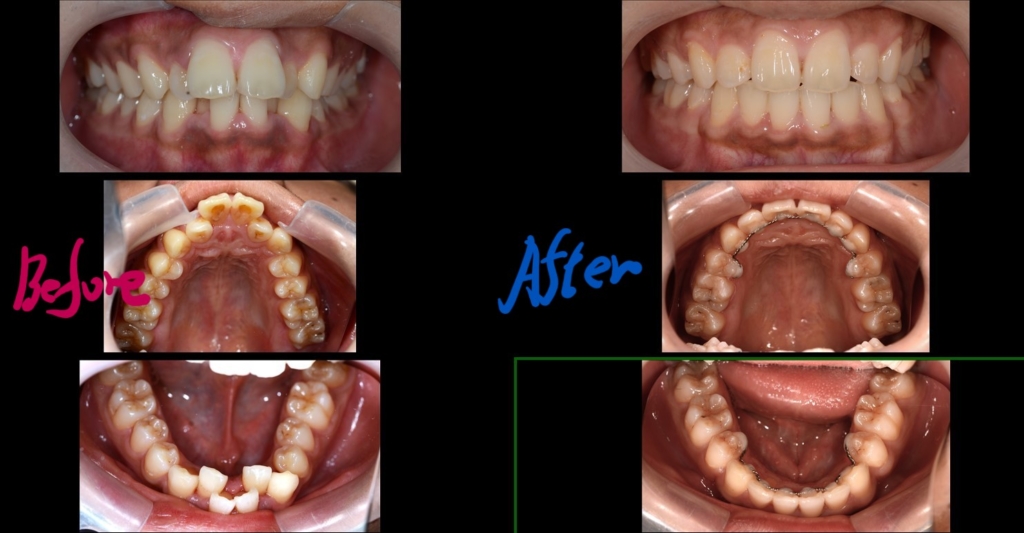

上の前歯が飛び出て、しかも凸凹もあるんです・・・

患者さんは、10代の男性(学生)です。

「上の2本の前歯が飛び出ているし、前歯全体がガタガタしているのをキレイにしたい」

という希望でした。

【Before】

#.顎と歯の不調和による叢生

と診断しました。

臼歯の咬合関係は特に問題なし。

【After】

【保定】 上下ともフィックスタイプ&クリアリテーナー

あらためて、矯正治療前後の歯並びと口元の変化を比べてみましょう。

治療後には、オトガイ部にあった梅干し状のシワが無くなっていることが分かります